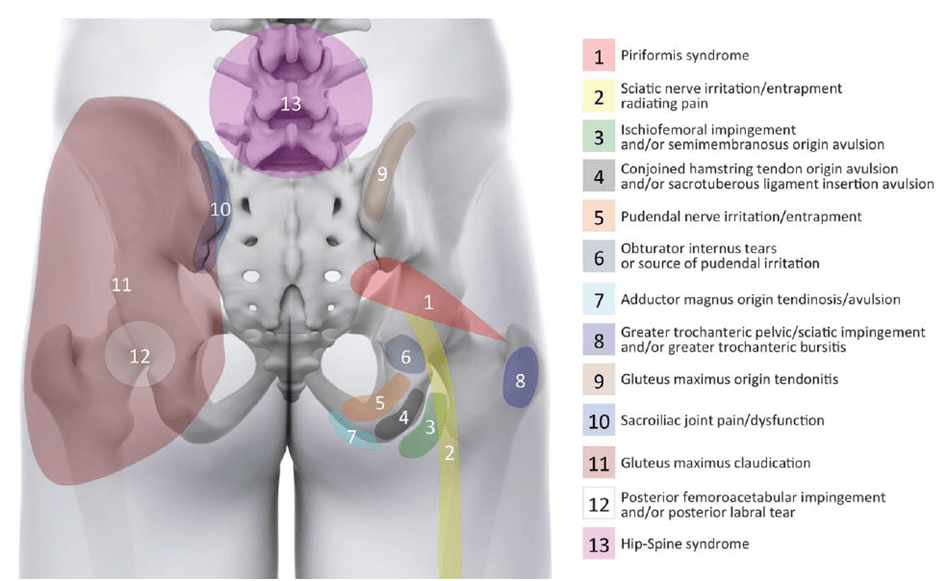

如果患者只报告臀部疼痛,那么可能存在多种潜在病症,这使得诊断非常困难。 以下是 戈麦斯-霍约斯等人 (2018),髋关节/臀部后侧疼痛的可能潜在原因:

我们的首要任务是检查腰椎,因为疼痛通常会传到臀部。 骶髂关节也会引起痛觉。 拉斯莱特群集可帮助确定这一诊断的可能性。 关于其他诊断,您可以在我们的频道中找到相关视频。